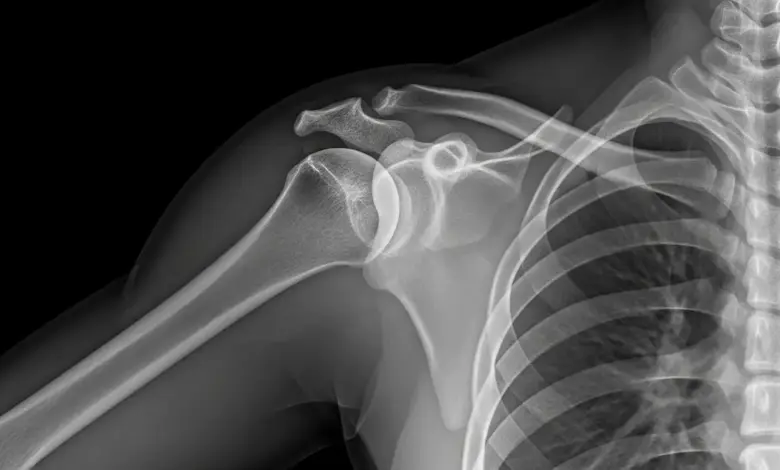

É uma causa frequente após quedas com impacto no ombro. A articulação acromioclavicular (entre clavícula e acrômio) pode sofrer lesão ligamentar e criar o aspecto de “degrau”.

A intensidade varia por grau de lesão e nem sempre exige cirurgia.

- Radiografias para ver fraturas e alinhamento articular.